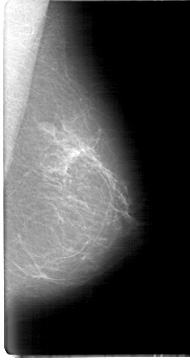

D_4070_1.LEFT_MLO

LEFT_MLO LINES 5386 PIXELS_PER_LINE 2836 BITS_PER_PIXEL 12 RESOLUTION 43.5 NON_OVERLAY